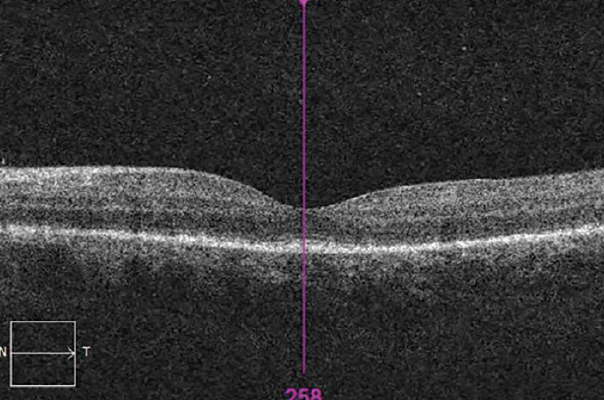

After the course of penicillin, the patient’s vision recovered and the rashes resolved. BCVA was 0.00 logMAR OD and 0.06 logMAR OS. Fundus examination showed no significant abnormality in either eye. OCT showed reduced irregularity and thickening of the RPE layer and a well-defined outer limiting membrane in each eye. There was complete resolution of SRF OD (Figures 8 and 9).

<p>Figure 9. OCT showing reduced irregularity and thickening of the RPE layer and well-defined outer limiting membrane OS.</p>

Figure 9. OCT showing reduced irregularity and thickening of the RPE layer and well-defined outer limiting membrane OS.